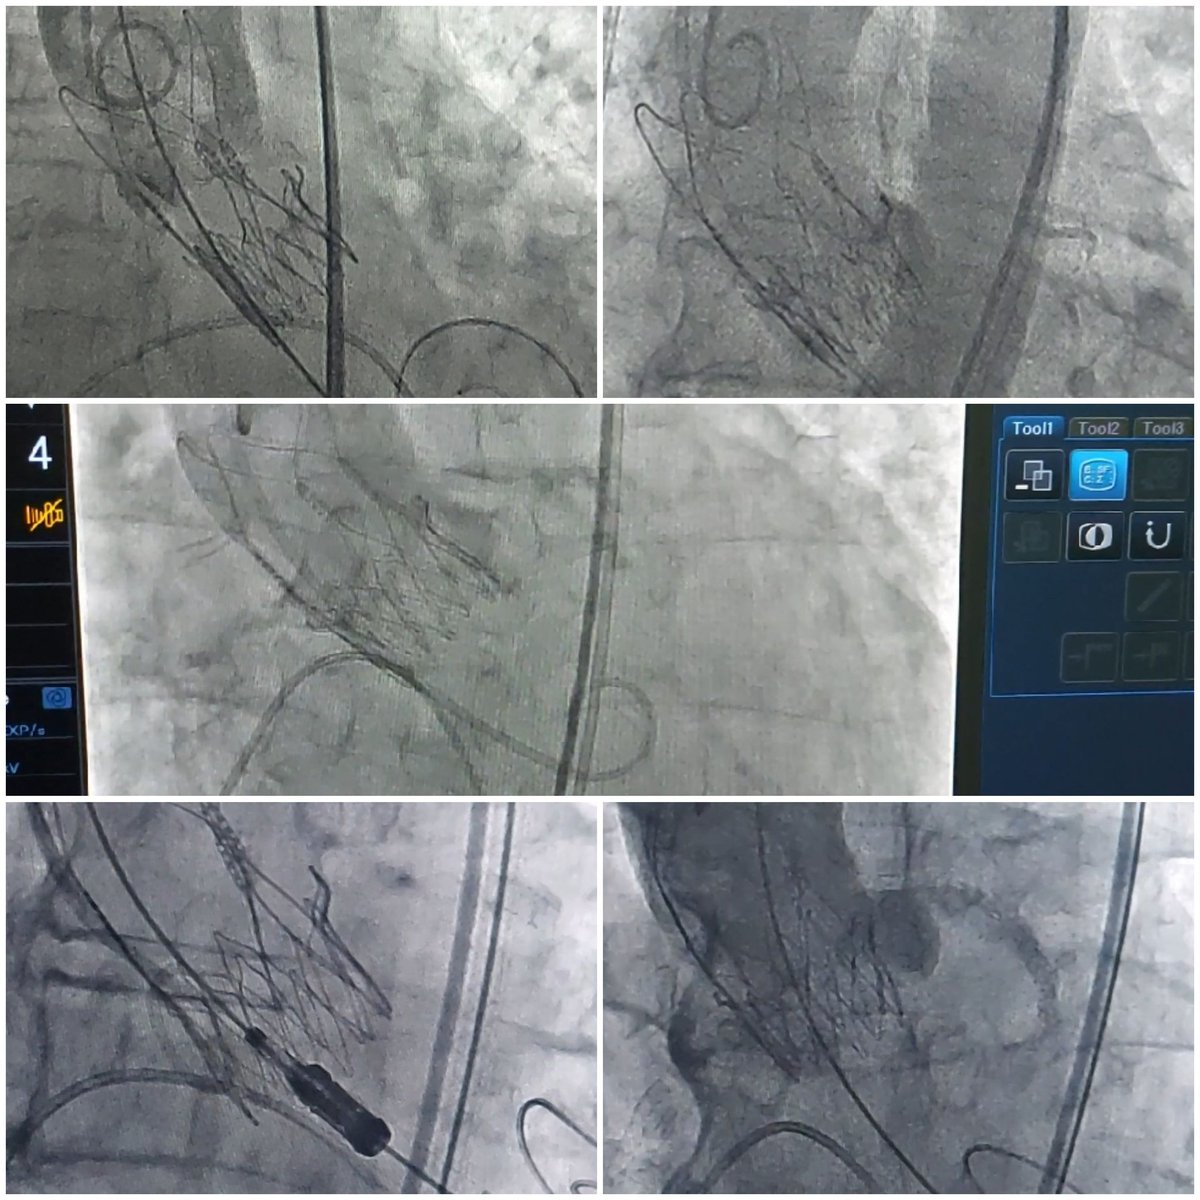

4th nicvd CTO workshop. 9 challenging cases. Retrogrades, ADRs and a lot more. @nicvdintvcard @nicvd_karachi @AllanaSalman @rzakir12 @ACCinTouch @SCAI @CtoEuro @md_SsAhmad @LAzzaliniMD @AKUGlobal @AkuCardiology @AnkurSethi2021 @esbrilakis @jas_sheerazi @escardio @shaoliang_chen

4

2

43